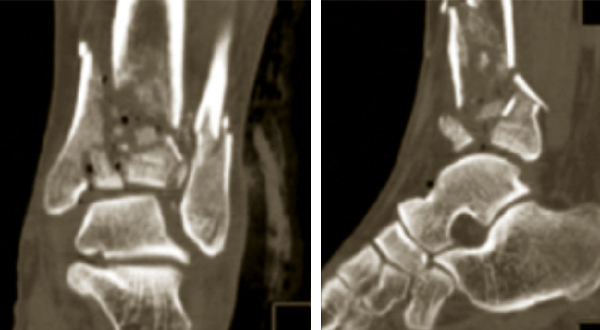

Fracture du pilon tibial

Scanner mettant en évidence une fracture du pilon tibial